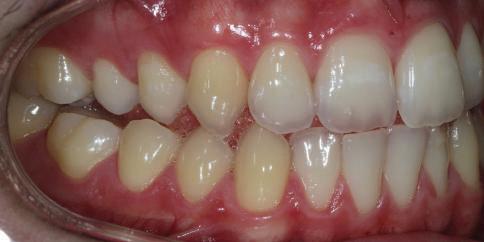

Dental Tribune Bulgarian Edition / октомври 2022 г.16 клиничен случай с алайнери Г орният латерален ре зец е вторият найчесто вродено липсващ зъб.1,2 Поради разполо жението му във видимата зона на усмивката лечение то на подобни случаи нала га мултидисциплинарен под ход, целящ отличен функцио нален и естетичен резултат. Налице са няколко лечебни мо далности, свързани с различ но разпределение на място то: първият вариант е орто донтско отваряне на място и възстановяване на липсва щия зъб с конструкция, под държана от съседните зъби3 или от имплант4, докато при втория подход разстоянията се затварят и премоларът заема мястото на канина.5 Изборът на лечебен подход трябва да бъде направен съв местно от зъболекар и паци ент въз основа на очакванията на последния и предвиди мостта на лечението. Множе ство фактори влияят върху това решение, като напри мер типа малоклузия, размера, формата и цвета на кучеш ките зъби6, оклузалните вза имоотношения (овърджет и овърбайт), лицевия профил, дължината на зъбната дъга и несъответствията в разме ра на зъбите.7 В настоящата публикация се разглежда случаят на жена в зряла възраст с вродена лип са на горен ляв латерален резец. Бяха приложени про зрачни алайнери за отваряне на място за единичен им плант и бяха постигна ти функционална оклузия и отлична естетика. ПРЕДСТАВЯНЕ НА СЛУЧАЯ Диагноза Пациентката бе на 32 годи ни, когато лечението започна, и първоначалното ѝ състоя ние бе следното (фиг. 1–3): липсващ горен ляв латерален резец; клас II, подклас I малоклузия; отклонение на горната сре динна линия вляво; Доклад на клиничен случай ЛЕЧЕНИЕ С АЛАЙНЕРИ НА ПАЦИЕНТ С АГЕНЕЗИЯ НА ЛАТЕРАЛЕН РЕЗЕЦ Д-р Iro Eleftheriadi и д-р Christodoulos Laspos, Гърция и Кипър Фиг. 1a–h Предоперативни лицеви и интраорални снимки. Фиг. 2a–e Дигитални модели преди началото на лечението. Фиг. 3 Панорамна снимка преди лечението. Фиг. 1a Фиг. 1d Фиг. 1f Фиг. 2a Фиг. 2d Фиг. 2b Фиг. 2e Фиг. 3 Фиг. 2c Фиг. 1b Фиг. 1e Фиг. 1g Фиг. 1h Фиг. 1c

Dental Tribune Bulgarian Edition / октомври 2022 г. 17клиничен случай с алайнери леко струпване в долната че люст; несъответствие по Болтън (мандибуларен излишък от 3.06 мм във фронталната зона и общо 1.47 мм); издължено лице с лицева аси метрия; конвексен профил с ретруди рана долна челюст и проми нентен нос. На мястото на зъб #46 бе на лице имплант, а зъби #16 и 26 са ендодонтски лекувани. Тези зъби бяха асимптоматич ни, затова бе взето решение да се прави релечение само при нужда. Мъдреците липсваха. Анализът на телерентгеногра фията (фиг. 4) показа ретрог натна мандибула (SNB: 74.2°) и нормална инклинация на резците както в